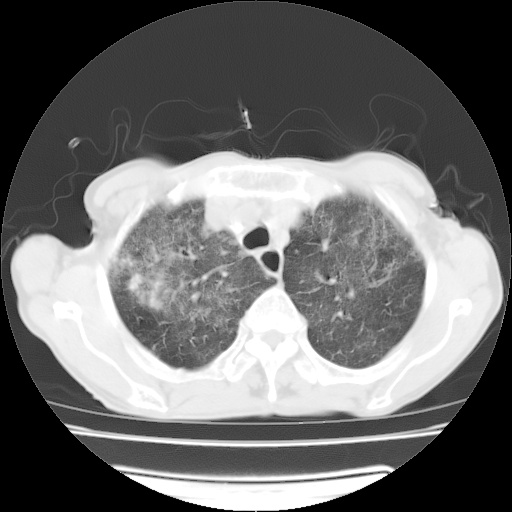

病人发热、气促就诊。原二周前已行ct扫描,当时诊断为双肺下叶、右肺中叶支气管扩张并感染,双肺上叶片状渗出性病变。今天复查胸部ct,双肺下叶支气管扩张并感染病灶较前明显吸收,但双肺上叶渗出性病变较范围较前明显增大。

现传今天ct图像给大家讨论。

双肺多发大片状、斑片状高密度渗出影,部分实变,考虑病毒性肺炎。